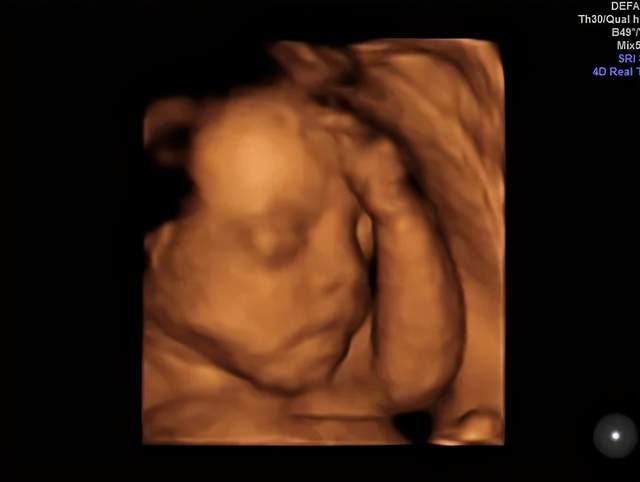

嗯,开始检查了!医生在妈妈肚子上涂了好多凉凉的东西,然后用一个小仪器在妈妈的肚子上探来探去。没多久,妈妈就看到了你的动态了哦!妈妈真的像在四维影院看电影一样的,看到你在肚子里各种欢腾的样子。

你看你爸爸,激动的一直说话,“老婆老婆!你看宝宝鼻梁多高,你看他还在吃手,你看他圆圆的脑袋好可爱啊……”宝贝,你爸爸是不是像个大孩子一样,看到你就手舞足蹈,语无伦次了。哈哈哈哈,你老爸让你一定要遗传他那活泼又搞笑的基因呢!

嘿嘿,下面照片就是你的“写真”,还是“裸体”的呢,不要害羞哈!这个可是爸爸妈妈送给你的礼物哦。等你长大了,看到在妈妈肚子里面的照片,是不是会很意外啊?嘿嘿,这个啊就是四维彩超的神奇功效啦,可以让爸爸妈妈看到你健健康康的成长,看到你欢快的动作还让爸爸妈妈稀里哗啦的留下了好多感动的眼泪呢。宝宝,爸爸妈妈等着你哦!

(转过来转过去,只为让医生和粑粑麻麻更清楚的看到我的盛世美颜)